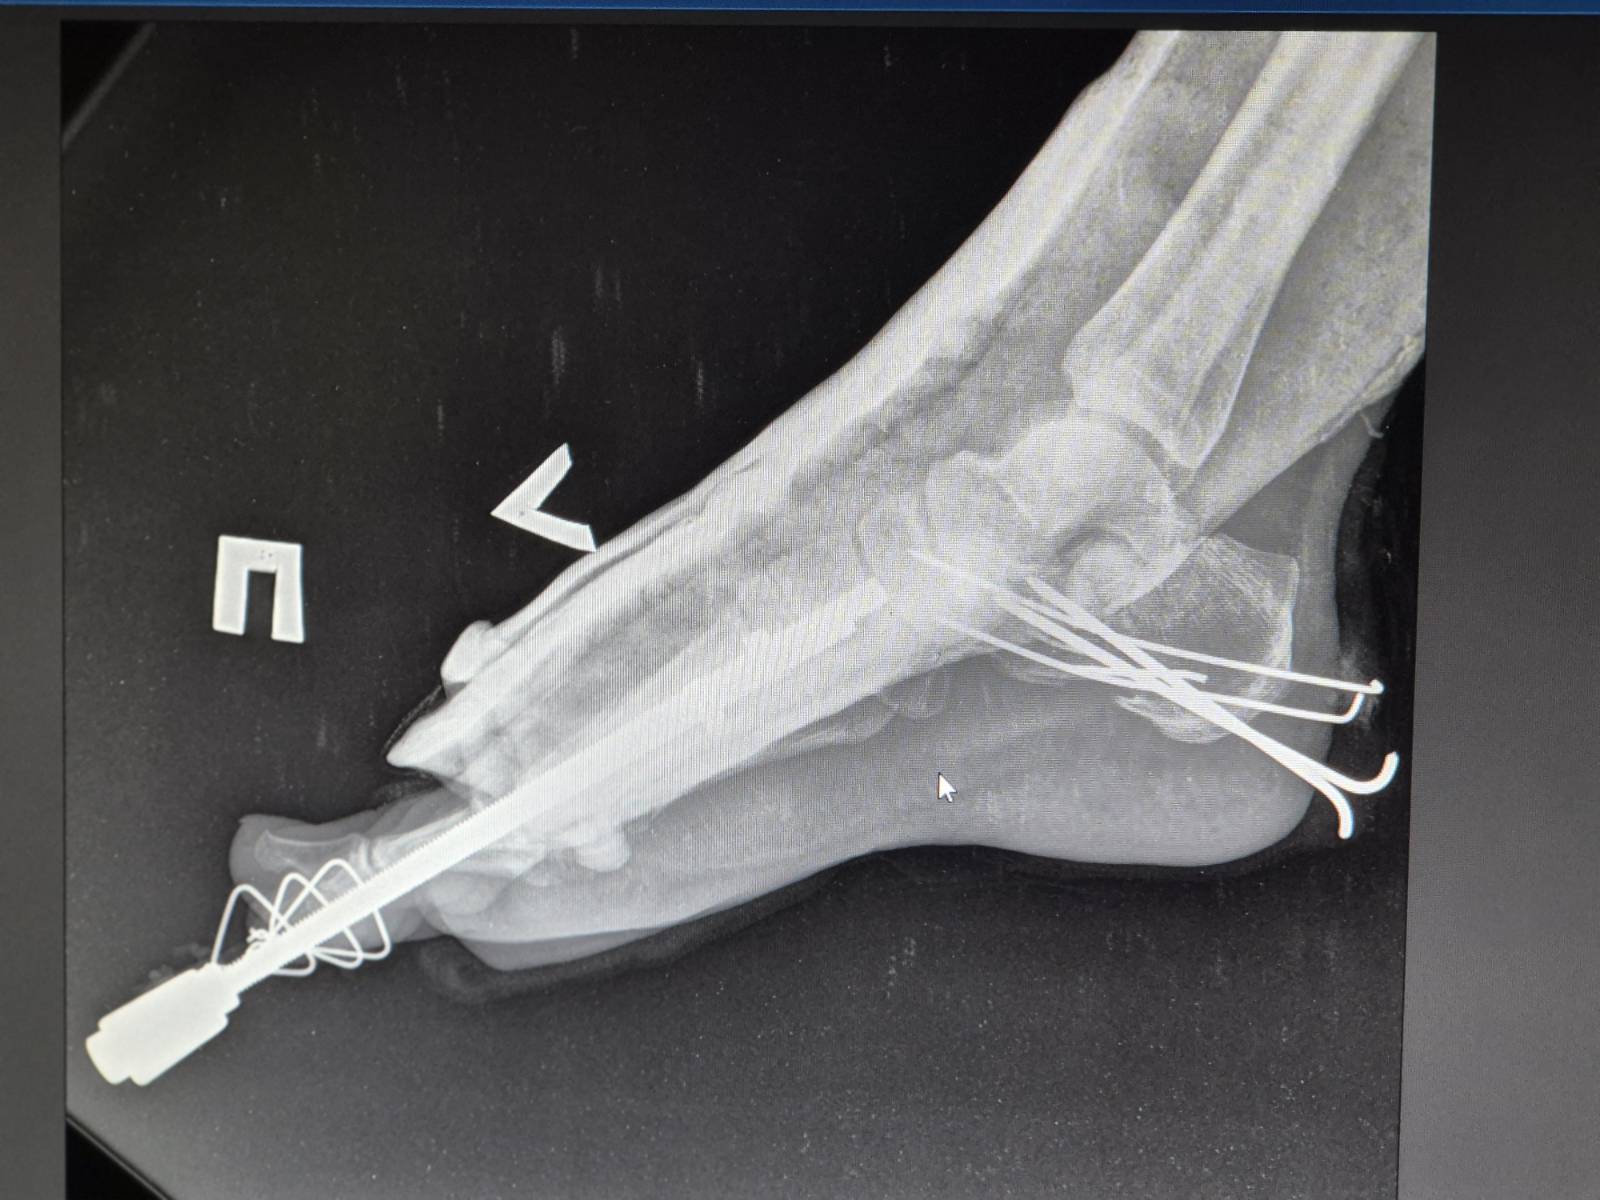

« L’une des patientes est une professionnelle de santé. Elle rentrait chez elle après le travail lorsque le drone a frappé le bus », explique Olha Severyn, anesthésiste de MSF à l’hôpital de Kherson. « Elle a subi de graves blessures aux jambes et aux pieds. Nous l’avons anesthésiée et opérée. » Une autre patiente, souffrant d’une grave fracture à la jambe et ayant perdu beaucoup de sang, a été traitée dès son arrivée. Les deux femmes sont actuellement dans un état stable.